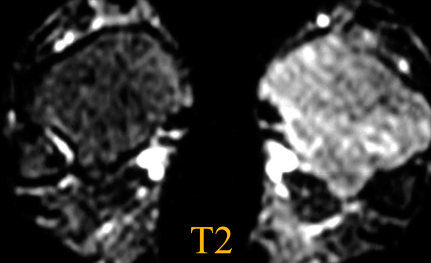

IRM

- Hyperémie locale (Se voit dans l’ensemble en scintigraphie)

- Préservation de composante graisseuse dans les zones touchées

- Zones plus actives = moelle en hyper T2